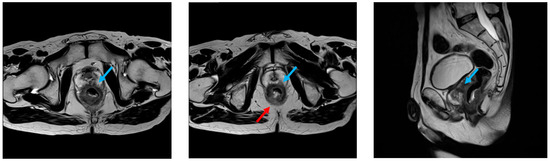

2.1. Patient